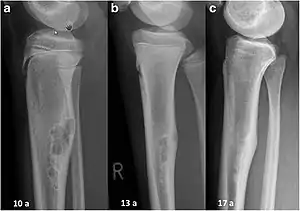

| Non-ossifying fibroma of tibia | |

The most common bone tumor is a non-ossifying fibroma.[4] Average five-year survival in the United States after being diagnosed with bone and joint cancer is 67%.[5] The earliest known bone tumor was an osteosarcoma in a foot bone discovered in South Africa, between 1.6 and 1.8 million years ago.[6]

Primary bone tumors

Primary tumors of bone can be divided into benign tumors and cancers. Common benign bone tumors may be neoplastic, developmental, traumatic, infectious, or inflammatory in etiology. Some benign tumors are not true neoplasms, but rather, represent hamartomas, namely the osteochondroma. The most common locations for many primary tumors, both benign and malignant include the distal femur and proximal tibia (around the knee joint). Examples of benign bone tumors include osteoma, osteoid osteoma, osteochondroma, osteoblastoma, enchondroma, giant cell tumor of bone and aneurysmal bone cyst.